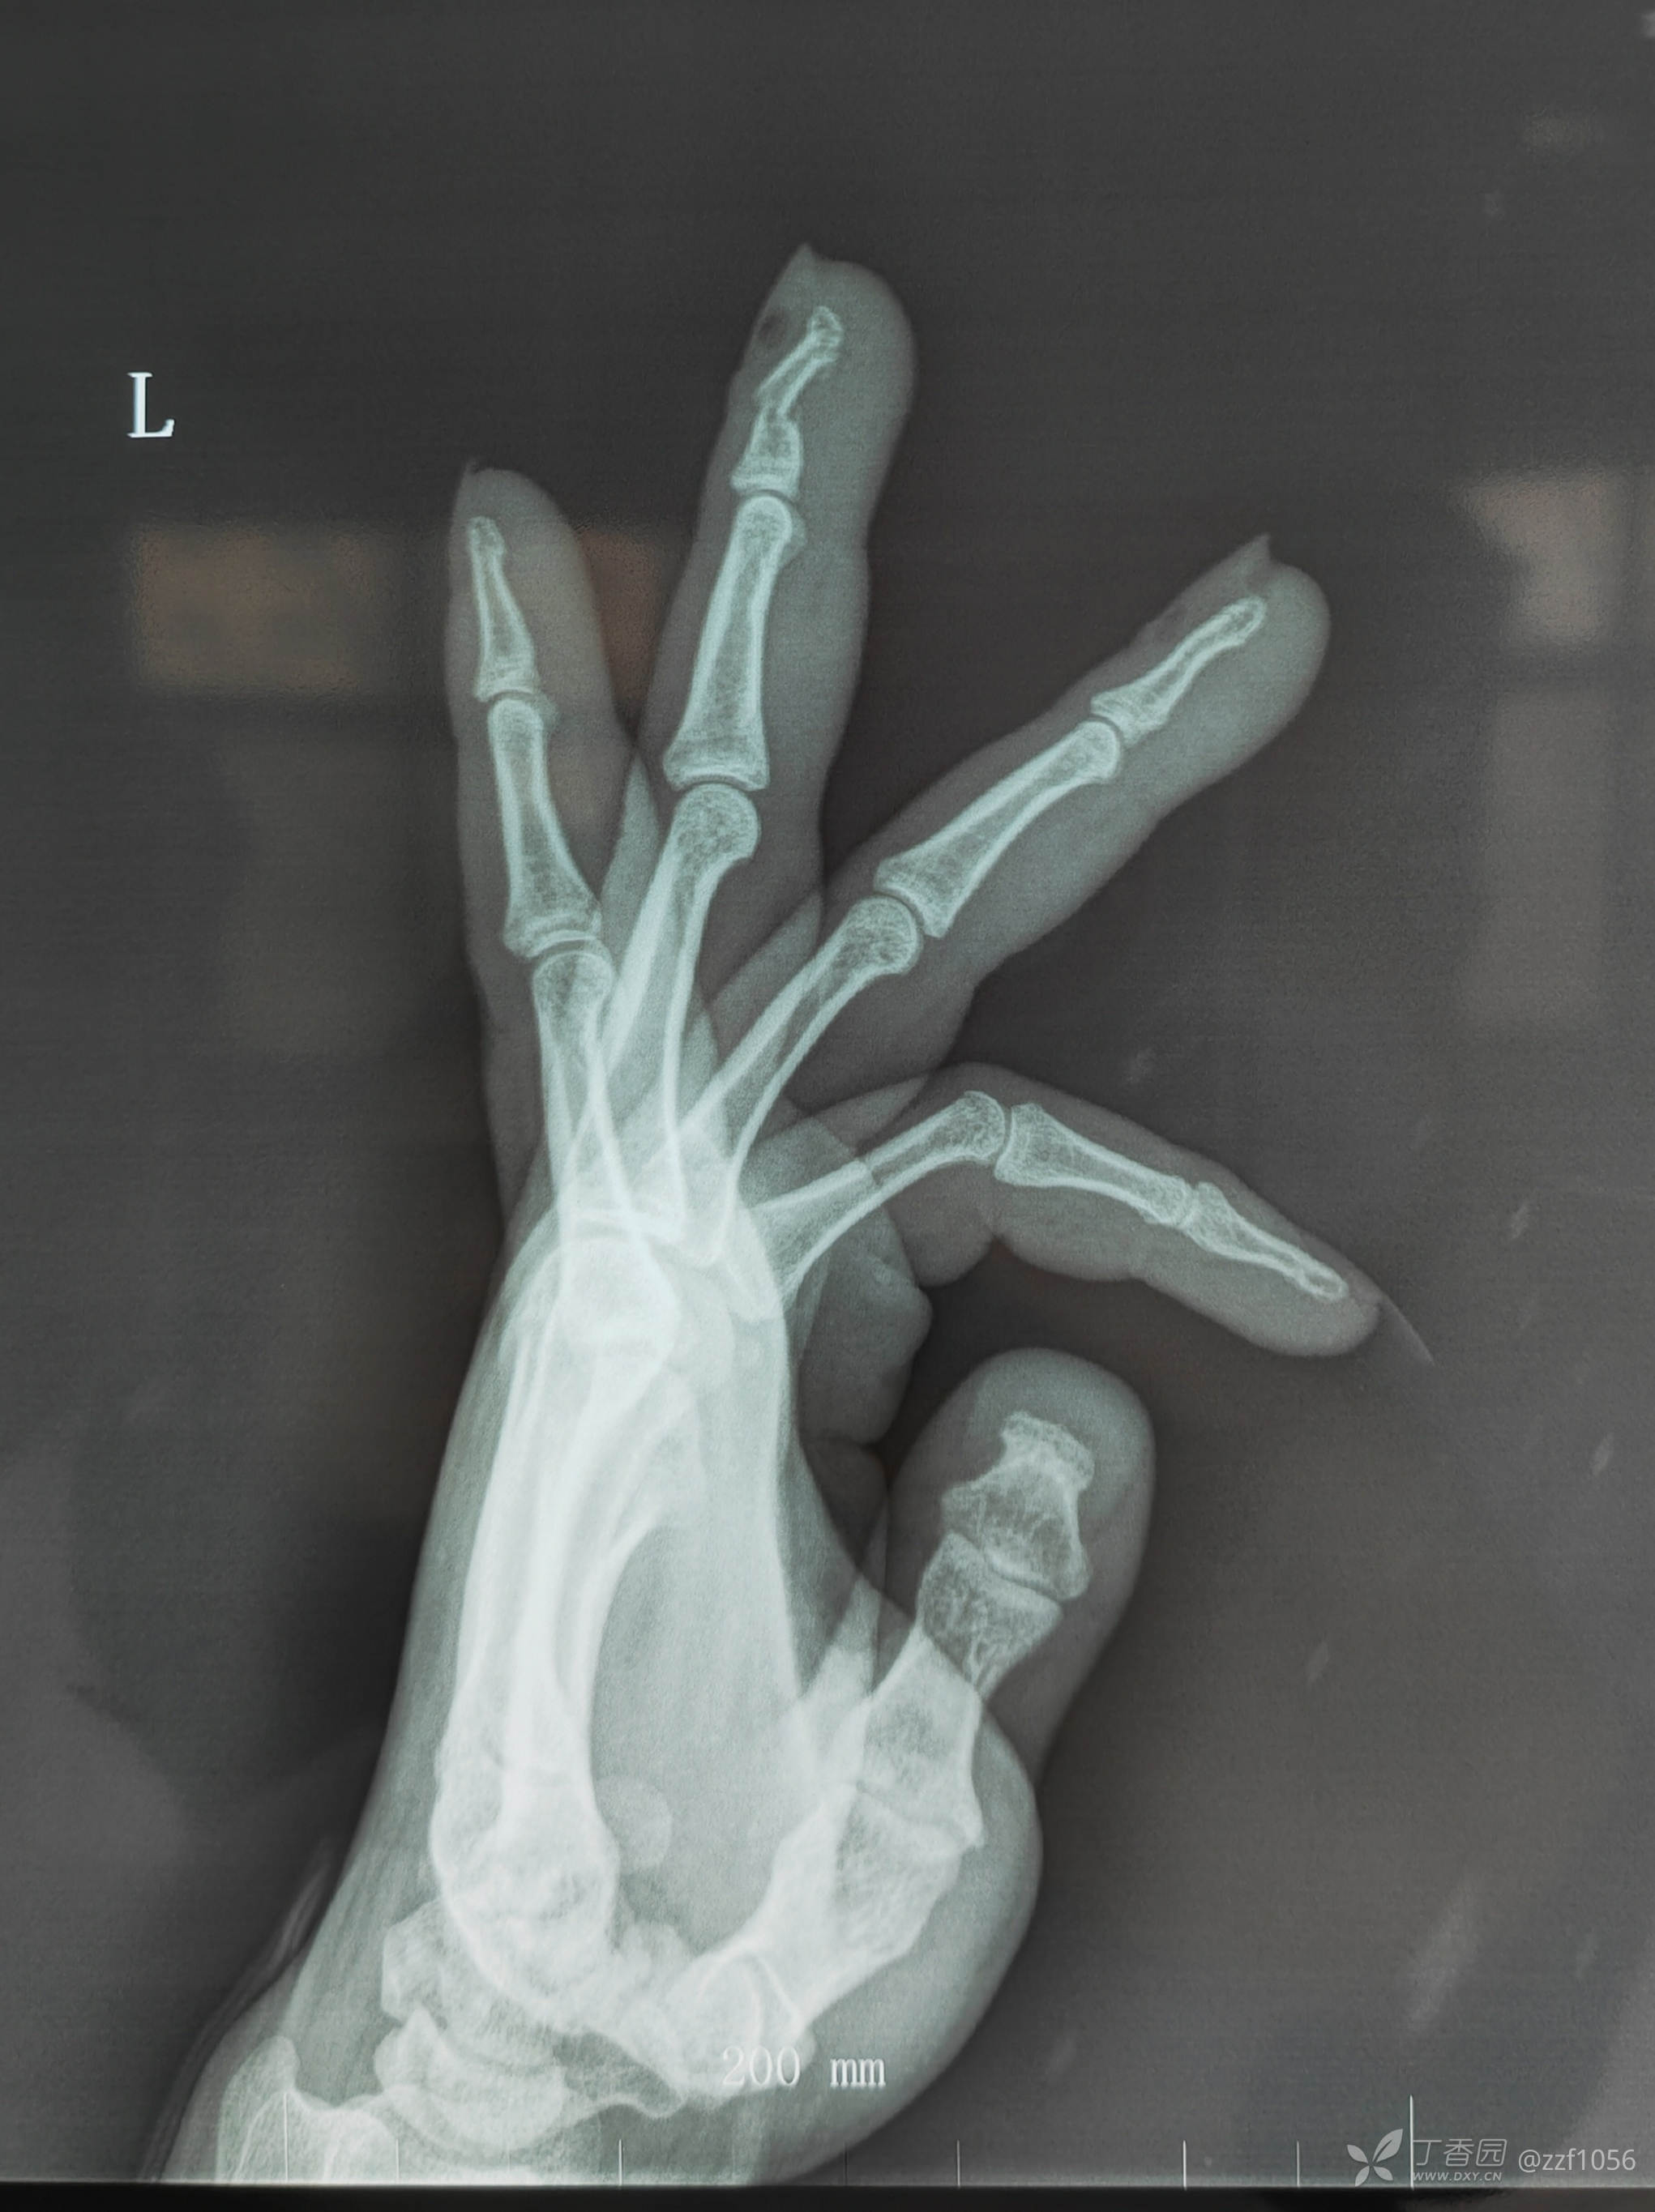

背侧成角折端嵌插千万不要以为直接就可整复,经验告诉我们闭复肯定会失败

甲床根部破裂嵌入折端,清理后撬拨复位,怎么固定?克氏针一枚还是两枚?纵行还是交叉?需要外固定吗?